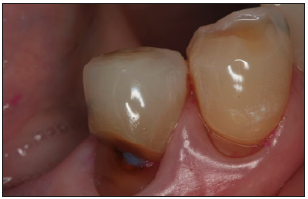

The incidence of root caries in the older adult has been estimated at approximately 1.6 root surfaces per 100 root surfaces at risk. The nature of the root caries appear to be more severe in males and most likely to affect the molar regions (Figure 1 and Figure 2). Significant factors associated with root caries include decreased salivary flow, impaired manual dexterity, and systemic conditions requiring medications that decrease salivary flow. Other risk factors influencing the higher incidence of root caries among the older patient include abrasion at the cementoenamel junction, fixed bridgework, removable partial dentures, long-term institutionalization, and soft diets consisting of refined sugars and sticky, fermentable carbohydrates. Root caries prevention and therapy include application of topical fluoride, dietary counseling, plaque control, and prevention of gingival recession.

Figure 1. Root caries. Courtesy of dentalcare.com

Figure 1